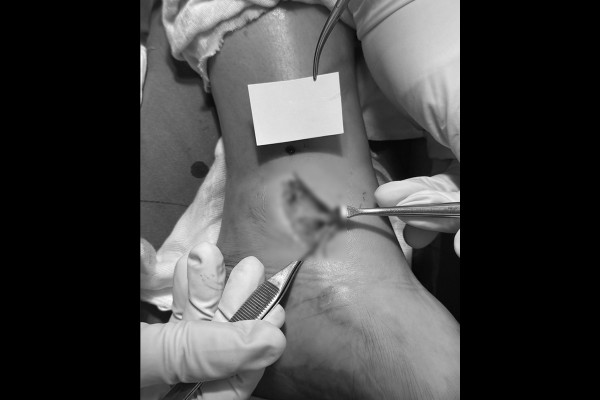

내측 삼각인대의 경우 최소 절개방식으로 봉합을 진행합니다. 먼저 수술실에서 파열된 삼각인대가 확인되고,

이후 잘 봉합된 삼각인대를 확인할 수 있습니다.